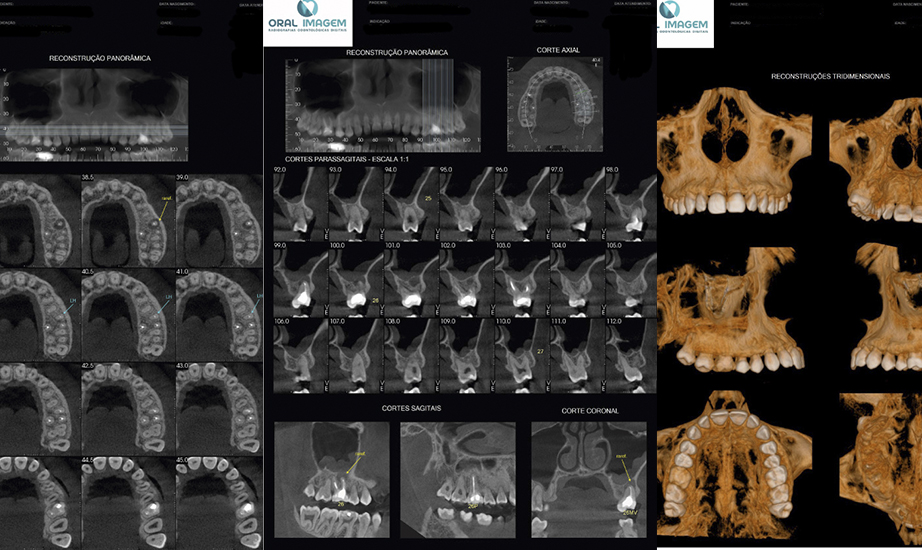

TOMOGRÁFIA DE ALTÍSSIMA RESOLUÇÃO